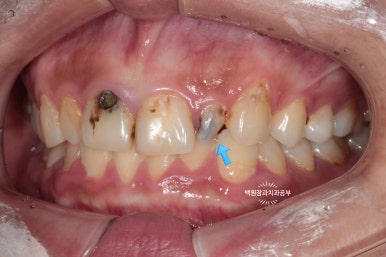

고개를 살짝 돌려 찍어본 사진에서 더 확연히 치아우식증( =충치)을 확인 할 수 있습니다.

딱 보기에도 치료가 아주 시급해 보이는 상황이었어요!!

그리고 화살표로 표시한 양쪽 작은 앞니는 왜소치로 그 크기가 2/3 정도로 작은 소견을 보실 수 있습니다.